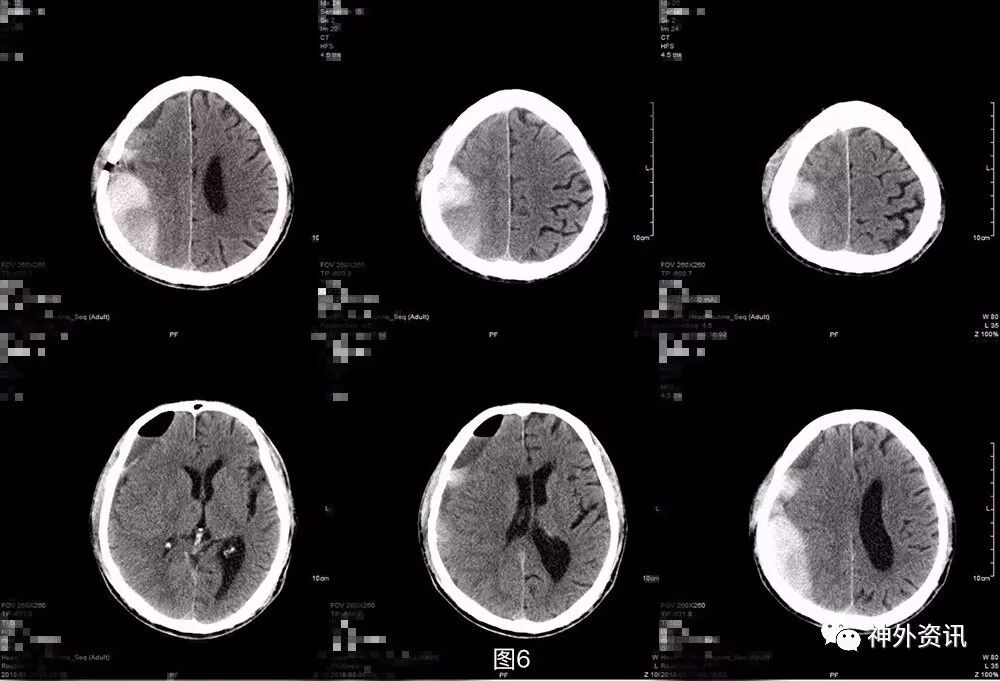

术后第2天复查头颅CT及MRI,提示局部仍有血肿,并见积气积液,占位较术前减少(图7)。

图7. 第三次术后第2天头颅CT及MRI提示:局部仍有血肿,可见积气积液,中线好转。